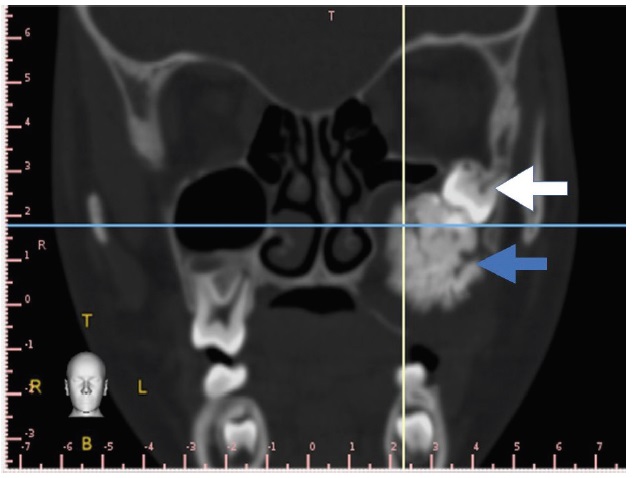

A seven-year-old male was referred for consult at the oral & maxillofacial surgery & implantology section of the hospital due to a large asymptomatic left maxillary mass resulting to a noticeable facial asymmetry. Clinical examination showed a solitary bony hard swelling on the left posterior maxilla exhibiting buccal and palatal expansion. Tooth mobility of the left premolars and absent permanent molar are likewise noted (Figure 1). CT scan showed an enlarging mass on the left posterior maxilla exhibiting an amorphous ovoid opacity surrounded by a defined radiolucent border overlying the crown of a permanent molar displacing the maxillary sinus floor without perforating it. (Figure 2) Based on the initial diagnostics considered impressions where ameloblastic fibro-odontoma and calcifying epithelial odontogenic tumor. Patient was admitted, prepared, once cleared underwent surgical enucleation of the mass under GETA via an intra-oral Lefort 1 incision, the mass was then submitted for histopathologic examination. 11 months after the operation (Figure 3), both clinical and radiographic findings show no sign of recurrence.

Figure 1. Clinical appearance. Mass producing facial asymmetry on left side of the patient, intra oral finding showing an evident bony hard mass on the posterior region of the left maxilla with noticeable altered eruption pattern of the left permanent molars.

Figure 2. Coronal cut CT scan showing impacted permanent molar and large amorphous opacity surrounded by a defined radiolucency.